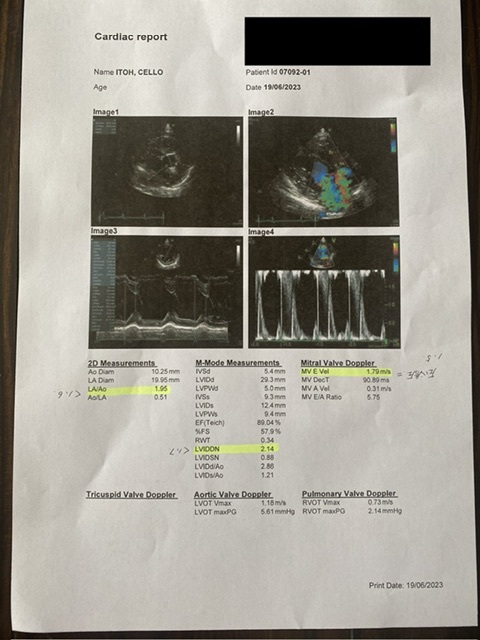

↑心臓のエコー

LA/AO (大動脈に対しての左心房の大きさ)正常値が1.6 チェロの場合1.95

LVIDDN(拡張期の左心室の大きさ)

正常値が1.7 チェロの場合2.14

MV E Vel(左室流入血流速)

正常値が1.5 チェロの場合1.79

上記の結果から心不全を起こしている。

MV E Velの数値も高いので、また肺水腫を発症する危険が高い。と説明を受けました。

前回検査をしたのが6月3日

その時と比べて

MV E Velの数値は0.78上昇

LVIDDNの数値は0.1上昇

その為、今飲んでいる利尿剤の量を増やすことになりました。

※フロセミド8/1錠を1日おきに服用していたのを1日2回毎日に変更となりました。

薬を増やすことはチェロの身体への負担は大きいと思います。それでも2回目の肺水腫を発症する前に気づくことができ、苦しい思いをしなくて本当に良かったと思いました。